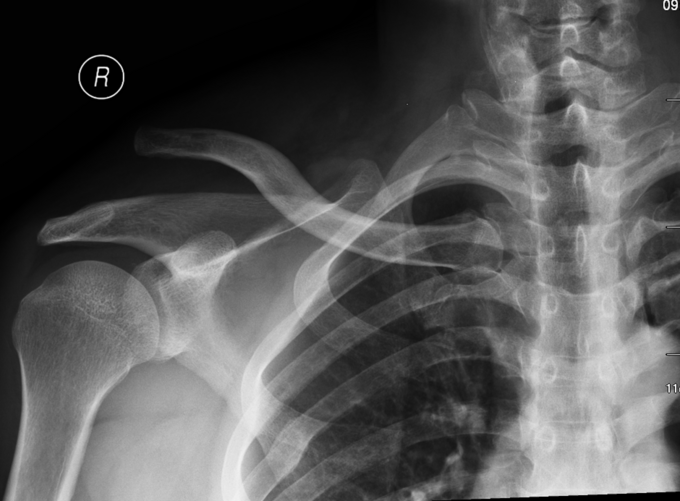

患者于2015年6月26日骑自行车摔伤时导致右肩部疼痛、活动障碍,意识状态可,被送至当地医院,行X线片检查示:右肩锁关节脱位,给予保守治疗。为求进一步治疗来我院,门诊行相关检查后,门诊以“右肩锁关节脱位”为诊断收住入院。

右肩外侧局部肿胀, 可见5x10cm不规整瘀斑,脱位锁骨远端端隆起于皮下,压痛不明显,未触及骨擦音及骨擦感,按压时有兵乓球感,右肩关节外展受限,手指活动灵活,锁骨下区及三角肌区皮肤痛觉无减退,桡动脉搏动有力,末梢血运良

诊断:右肩锁关节脱位 入院后完善检查,完善心电图,生化检查后。局部消肿后,查无手术禁忌症后行右肩关节脱位锁骨钩钢板内固定术